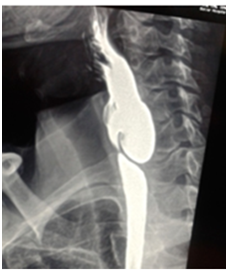

All six patients were symptomatic Four of patients were male. Age of patients was 65 to 80years. Four of patients came with dysphasia aspiration, halitosis, and malnutrition and regurgitation, one of this patient present three period with aspiration pneumonia and hospital admission. One of patients underwent endoscopic diverticulotomy and 24 hour after this procedure present with odynophagia, fever and neck subcutaneous emphysema With B-swallow perforation of diverticula was demonstrated, this patient underwent neck exploration and diverticulectomy and drainage. Diagnostic tools of five cases was B-swallow and esophagoscopy (Figures 1-5). One came with food marital retention and pain and neck mass tender mass. One patients referred with erithem, redness and criptation of neck with diagnosis of diverticulitis (Figures 6 & 7). Two cases underwent flexible endoscopic diverticulotomy, one failed and another ones complicated with perforation. The most common surgical approaches was diverticulectomy and myotomy in four patients (Figures 8 & 9). Food debris was present in one patient (Figure 10). Two of patients underwent diverticulectomy without myotomy. Complication and mortalities were zero. In two years flow-up, Outcome was good.

Figure 1 Show swallow of a 75 year old man with huge Zenker's diverticulum.

Figure 2 Show swallow of a 85 year old woman with huge Zenker's diverticulum.

Figure 3 Show swallow of a 65 year old man with huge Zenker's diverticulum.

Figure 4 Show swallow of a 80 year old man with huge Zenker's diverticulum.

Figure 5 Show swallow of a 78 year old man with huge Zenker's diverticulum.